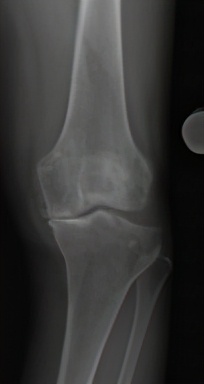

图1 膝骨关节炎x片表现:b中期

膝骨关节炎的早期表现为膝关节疼痛,随着病情进展,会出现疼痛加重并活动受限,关节畸形。患了膝骨关节炎该如何治疗?首先需明确, 治疗的目的主要是2个,即解决疼痛,改善关节功能。 解决了这两个问题,最终就会实现生活质量的提高。那么如何缓解疼痛?怎样改善功能?这是每个膝骨关节炎患者最关心的问题,这需要根据病情的严重程度,采取个体化的治疗手段。患者希望以最小的代价获得最满意的疗效,这也是医生不竭的医术追求。